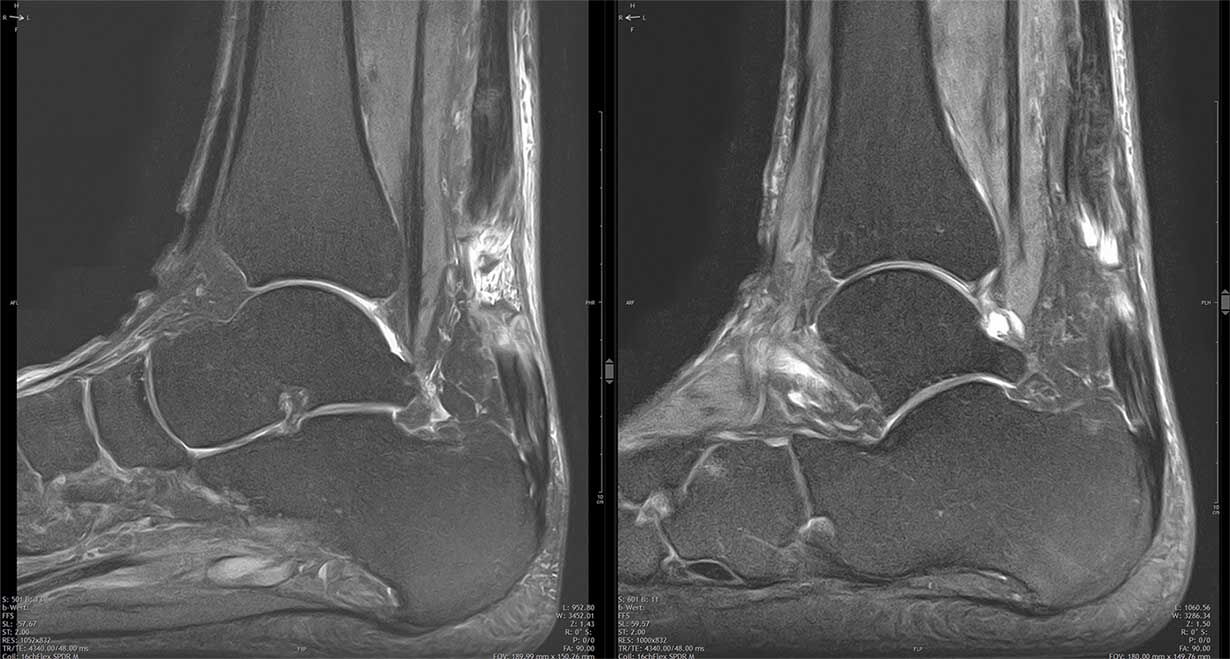

. Zwei MRT-Aufnahmen eines Knöchels mit Fokus auf Knochen und Bänder.

Beidseitige Achillessehnenruptur nach antibiotischer Therapie mit Fluorchinolonen